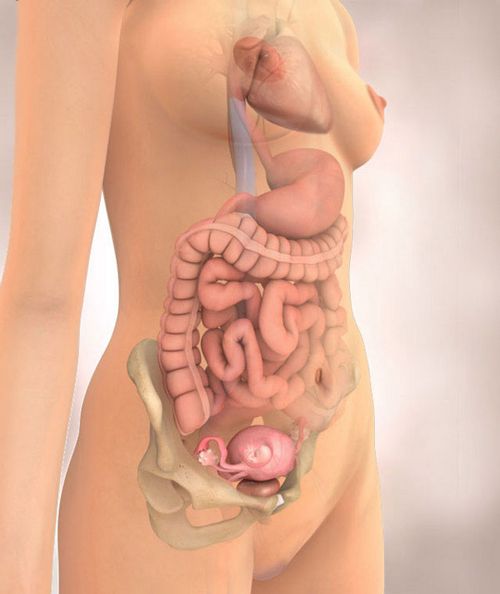

Вагітність 11 тиждень - це етап, коли лікарі Вашого малюка вже повноправно називають плодом. Ви з малятком виконали грандіозну роботу, тепер він буде стрімко рости.

11-а тиждень вагітності - це ще більше удосконалення маленького організму. Малюк буде стрімко рости до 20-го тижня. Уже все системи та органи функціонують по повній! Травний тракт вдосконалюється, відбувається поповнення прямої кишки. Малюк ковтає навколоплідної рідини, навіть позіхає. Розмір плоду на 11 тижні вагітності наведено в таблиці.